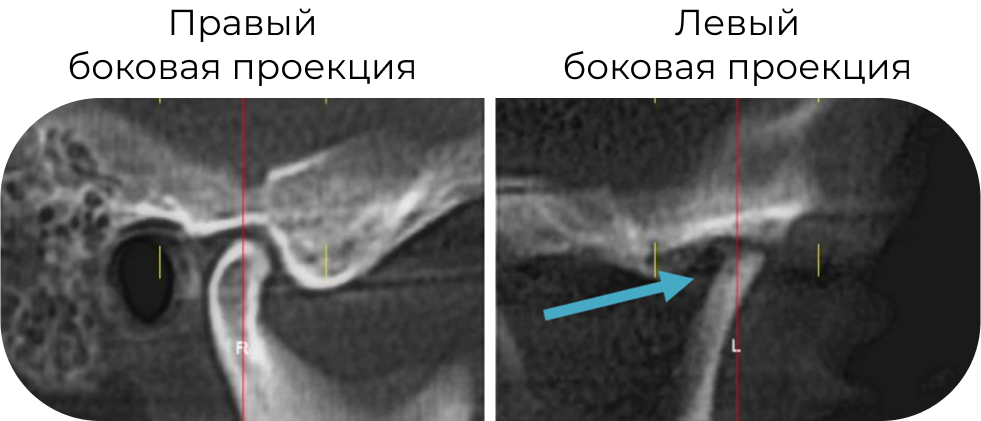

КТ до лечения: начальные признаки фиброзного анкилоза!

МР-картина выраженных дегенеративных дистрофических изменений левого мыщелкового отростка и деформация головки, учитывая в анамнеза травму 15 лет назад возможно травматического генеза.

Деформация с признаками застарелого повреждения промежуточной зоны, дислокация и малоподвижность суставного диска слева (признаки адгезии диска). Признаки гипомобильности ВНЧС слева.

Справа отмечается вентролатеральная дислокация суставного диска с репозицией при открывании рта.

Умеренный синовит.